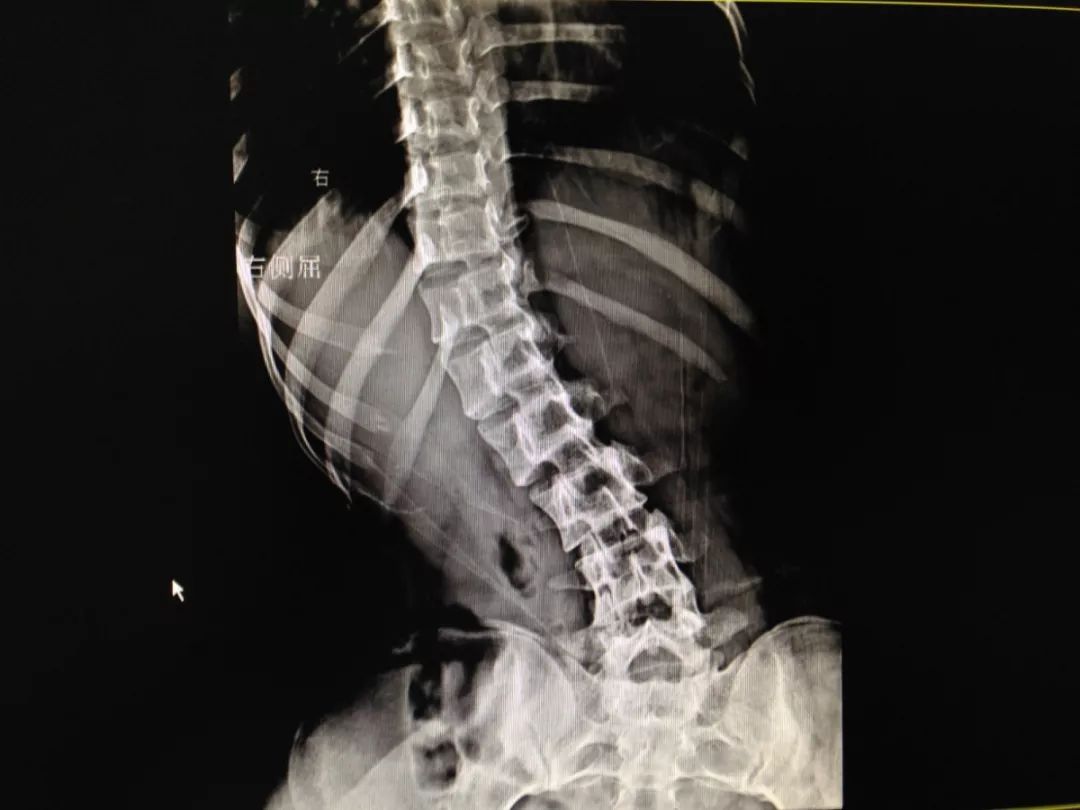

18岁脊柱侧弯术前